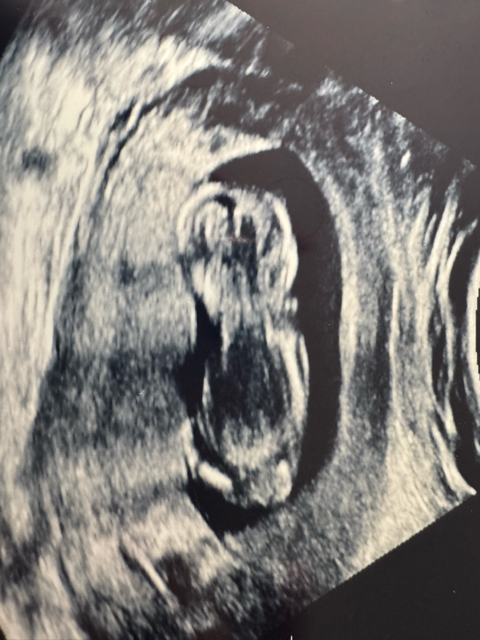

Second ultrasound 🥹

Had a ultrasound today 🥹

Also, what do you guys think this little nugget is? Boy or girl?